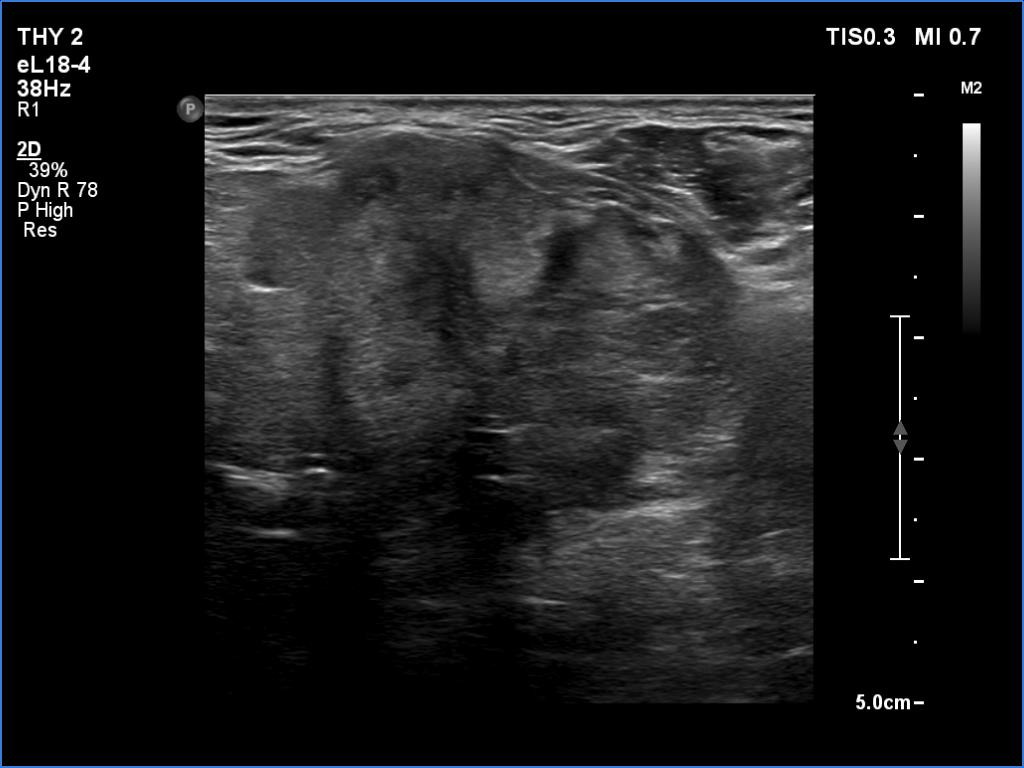

Ultrasonography. The right lobe was echonormal and intact. A large mass occupied almost the entire left lobe. On this side, normal thyroid tissue could only be identified in the dorsal part. The mass was composed of echonormal and hypoechoic areas, had macrocalcifications, irregular intranodular vascularity and proved to be very hard on elastography. There were multiple lymph nodes in III, IV and V left neck compartments. One of the nodes was in close proximity to the jugular vein and was suspicious of having broken into the vessel. The trachea was significantly narrowed at the lower level of the thyroid.

2. There are several remarkable findings in this case, e.g., the destruction of the left lobe by the tumor, the elastography pattern, the relation of the largest metastatic lymph node and the jugular vein, the ultrasound demonstration of the trachea' stricture.